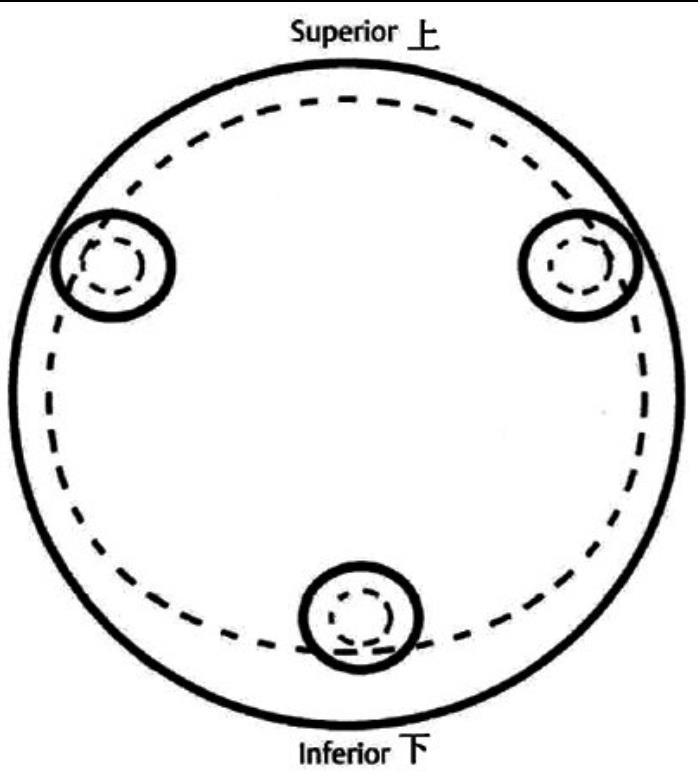

2、标准放置螺钉为倒三角形,其中下方螺钉在股骨矩,后方螺钉在后方骨皮质、研究发现倒三角形平行三枚螺钉能提供最佳的固定强度;

空心钉固定的三原则:“贴边、平行、倒品”

1、贴边是指3枚螺钉在股骨颈内,尽量靠近外围皮质。这样3枚螺钉作为一个整体,对整个骨折面可形成面状加压,如果3枚螺钉不够离散,更趋于点状加压,稳定性较差,不能较好地对抗扭转和剪切。

有研究显示,在侧位片上,螺钉的前后分布越分散,骨折不愈合发生率越低。J Bone Joint Surg Br. 2005 May: 87(5): 632-4.

图1 3枚螺钉在股骨颈内的理想位置

2、倒品有更明显的生物力学优势,CORR曾发表美国学者的一项生物力学研究,对比两种固定方式出现再骨折的负荷大小,发现倒三角再骨折的平均负荷11330N,而正三角仅7795N,差异明显,也就是说倒三角形固定可使再骨折的负荷提升45%。

图2 倒品字固定

3、平行生物力学更稳定。